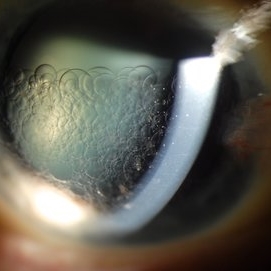

Retention of Perfluorocarbon in Anterior Chamber

Mar 1 2017 by Philip J. Polkinghorne, MD

Slit lamp photograph takien one week after retinal detachment surgery where perfluorocarbon liquid was used to re-attach the retina.

Photographer: Alex Fraser

Condition/keywords: perfluorocarbon fluid, retained perfluorocarbon, retina surgery complications